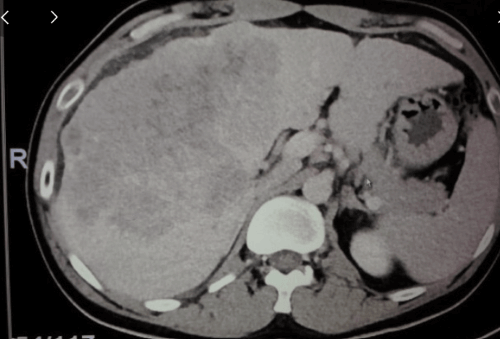

종양이 매우 크고 전이도 있고, 또 혈관 침범도 있는 전형적인 진행성 간암에서 표준 치료는 이 면역 관문 억제제, 면역 항암제를 쓰는 것입니다.

종양이 클수록 또 전이가 많이 있을수록 혈관 침범의 정도가 심할수록 치료 효과가 떨어지는 건 맞는데, 굉장히 심한 환자에서도 효과가 확실하게 나타나는 분들은 종양이 완전히 사라지는 걸 볼 수 있습니다.

물론 여기 그래서 이제 너무 환상을 가지시면 안 되지만, 모든 환자에서 이런 반응이 나타나면 참 좋겠죠. 하지만 그렇지 않습니다. 일정 비율의 환자에서 이렇게 종양이 완전히 사라지는 걸 경험할 수가 있는데요. 그거를 완전 반응이라고 합니다.

이 임상 시험을 통해서 이 간암의 면역 관문 억제제 효과를 봤더니, 완전 반응이라고 말씀드렸잖아요. 이 영상 검사를 했을 때, 암이 안 보이는 그런 완전 반응이 8% 나타났습니다.

그러니까 100명을 치료하면 한 여덟 명 정도에서 진행성 간암에 대한 완전 반응이 나타난다는 거다. 예전하고 비교해선 굉장히 높은 수치입니다,